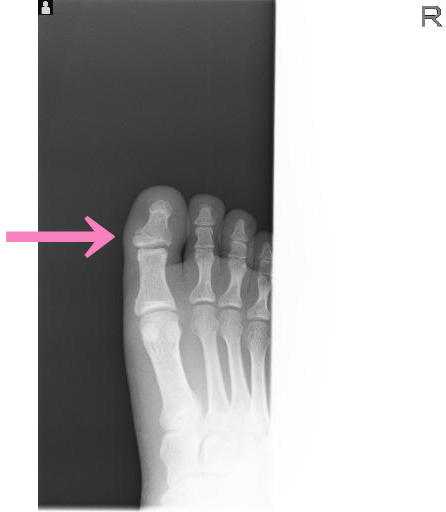

運動中ではないですが、靴を履くときに履き損ね、

足の親指を突き指したと御来院。

足を診せて頂いた瞬間に「たぶんこれは突き指ではなく骨折でっせ・・・」

やはり残念な結果でございまして、

確定診断のため、近隣整形外科へレントゲン依頼をしたところ、

結果は同じで足の親指「末節骨骨折」

基本的に足の指の骨折は、骨片(破片)が関節内に挟まったりしない限り、

手術等は行わず、保存的に固定をして経過を診ることが多いです。